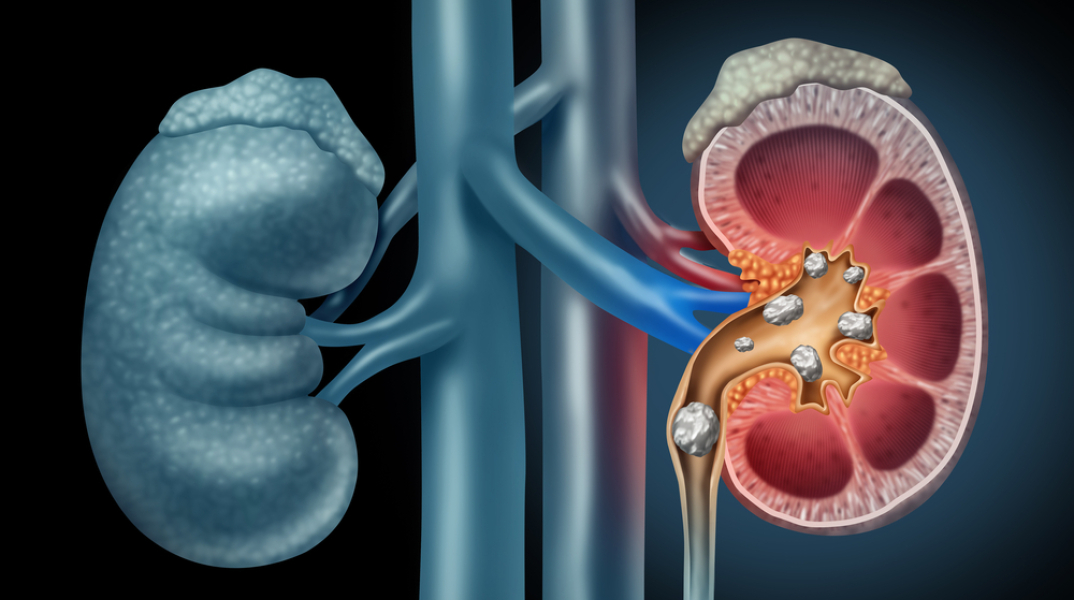

Μία διαταραχή που προσβάλλει το 5-10% του γενικού πληθυσμού είναι ο σχηματισμός λίθων στους νεφρούς. Η συχνότητα της νεφρολιθίασης έχει διπλασιαστεί τις τελευταίες δεκαετίες, ενώ φαίνεται πως είναι λίγο συχνότερη στους άντρες απ' ό,τι στις γυναίκες. «Αν και η διαταραχή μπορεί να έχει πολλές αιτίες, η συχνότερη αιτία νεοδιαγνωσθείσας νεφρολιθίασης είναι ο πρωτοπαθής υπερπαραθυρεοειδισμός», λέει εκ μέρους της Ελληνικής Ενδοκρινολογικής Εταιρείας η κυρία Εύα Κασσή, καθηγήτρια Ενδοκρινολογίας στην Ιατρική Σχολή του ΕΚΠΑ και επιστημονική υπεύθυνη του Κέντρου Εμπειρογνωμοσύνης Διαταραχών Μεταβολισμού Ασβεστίου και Φωσφόρου στο Νοσοκομείο «Λαϊκό».

Η κάθοδος των λίθων του νεφρού στο κατώτερο ουροποιητικό σύστημα (ουρητήρας, ουροδόχος κύστη) μπορεί να είναι επώδυνη, προκαλώντας κολικούς ή μπορεί να προκαλέσει απόφραξη ή/και λοίμωξη του ουροποιητικού συστήματος. Σε αντίθεση με τη νεφρολιθίαση, η νεφρασβέστωση είναι η διάχυτη εναπόθεση αλάτων ασβεστίου στο νεφρό, που συνήθως δεν δίνει συμπτωματολογία ή μπορεί να προκαλεί πολυουρία και πολυδιψία. Τόσο η νεφρολιθίαση όσο και η νεφρασβέστωση μπορεί να οδηγήσουν σε χρόνια νεφρική ανεπάρκεια.

Στην πλειονότητα των περιπτώσεων, οι λίθοι είτε είναι αμιγώς ασβεστίου (οξαλικούή φωσφορικού) είτε μεικτοί λίθοι ασβεστίου και ουρικού οξέος. Σε μικρότερο ποσοστό (5-10% των περιπτώσεων) πρόκειται για λίθους αμιγώς ουρικού οξέος. Η υπερασβεστιουρία, δηλαδή η αποβολή μεγάλης ποσότητας ασβεστίου με τα ούρα, αποτελεί τον συχνότερο προδιαθεσικό παράγοντα με νεφρολιθίαση. Ανευρίσκεται στο 30-60% των πασχόντων από αυτήν. «Η διερεύνηση και αντιμετώπιση των ασθενών με νεφρολιθίαση αφορά πολλές ειδικότητες (π.χ. ουρολόγοι, νεφρολόγοι). Ωστόσο ουσιαστικός είναι ο ρόλος του ενδοκρινολόγου, εφ’ όσον οι συχνότερες από τις αιτίες που προκαλούν ή προδιαθέτουν σε νεφρολιθίαση αφορούν σε ενδοκρινικές/μεταβολικές διαταραχές», τονίζει η κυρία Κασσή.